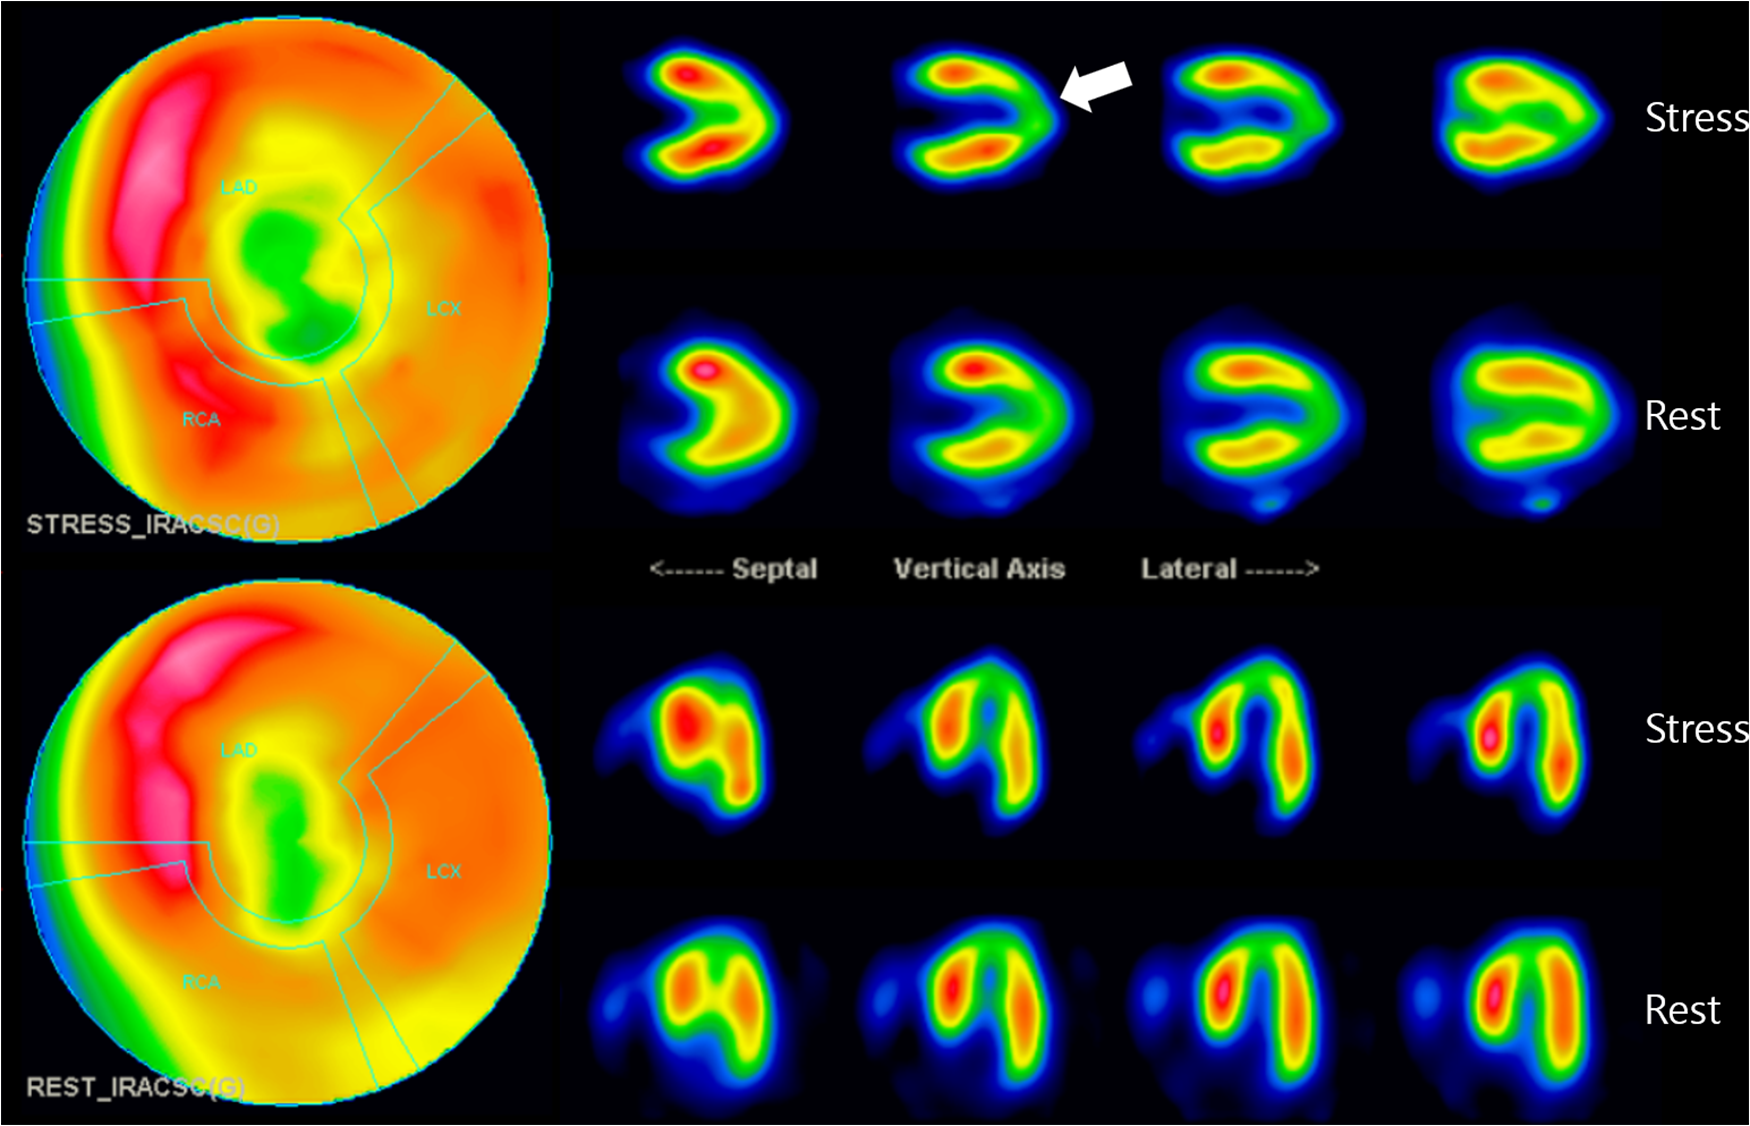

To determine its functional significance, Tc-99 m methylisobutyl isonitrile single photon emission computed tomography (SPECT) was additionally conducted. It demonstrated a medium-sized, moderate fixed perfusion defect around the apex, downstream to the bridging segment of the LAD, suggesting MI (Figure 3). The cardiac SPECT/CCTA hybrid imaging also confirmed excellent correlation between the extent of perfusion defects and the anatomical location of MB (Figure 4A), which was also correlated with CAG finding (Figure 4B).

Figure 3

Myocardial perfusion SPECT imaging: SPECT scan showed medium-sized, non-transmural infarction around the apex (whitish arrow). This defect correlates to the downstream myocardium to the bridging segment of the mid-LAD, as marked by arrows. LAD, left anterior descending coronary artery; SPECT, single photon emission computed tomography.

Non-invasive modalities include CCTA, stress gated SPECT, and stress echocardiogram. CCTA is able to identify bridging segment surrounded by myocardium (17), whereas stress gated SPECT can visualize myocardial perfusion defects then quantify the degree of myocardial ischemia (18). In the present case, we utilized the myocardial perfusion SPECT. Although most cases of MB can be found in anatomical imaging modalities, functional imaging like myocardial perfusion SPECT can also be feasible and useful to evaluate its functional significance in the form of perfusion defects (19). Lee and his colleagues demonstrated that high-grade MB could induce perfusion defects on territories of LAD and its branches in dipyridamole TI-201 SPECT findings (20). Such findings may reflect the degree of luminal narrowing by systolic contraction (18). A retrospective study by Huang et al. showed abnormal myocardial perfusion in patients with MB at the middle portion of LAD (21).